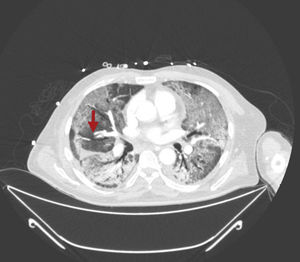

Paciente de 64 años, como único antecedente personal hipertenso, ingresa en la UCI con diagnóstico de SDRA grave secundario a neumonía bilateral por COVID-19. En radiografía de tórax se observa un patrón alveolointersticial bilateral que afecta más al pulmón derecho, sobre todo al campo medio (fig. 1, indicadores flechas). En la analítica destaca un dímero D muy elevado (28.970ng/ml) y ante la sospecha de TEP se realiza ecocardiografía transtorácica apreciándose sobrecarga de presión de VD con signo de McConnell positivo. Dado los hallazgos ecocardiógrafos, se inició tratamiento anticoagulante con heparina de bajo peso molecular (enoxaparina 1mg/kg/cada 12h) y se solicitó angio-TAC torácica para confirmación diagnóstica, evidenciándose defecto de repleción en arteria del segmento lateral del lóbulo medio (flechas en figuras 2 y 3) en relación con TEP. Además existe una afectación difusa bilateral y extensas áreas de patrón en empedrado en relación con el proceso infeccioso vírico (figs. 2 y 3). Se mantuvo el tratamiento anticoagulante hasta el alta sin complicaciones hemorrágicas asociadas.